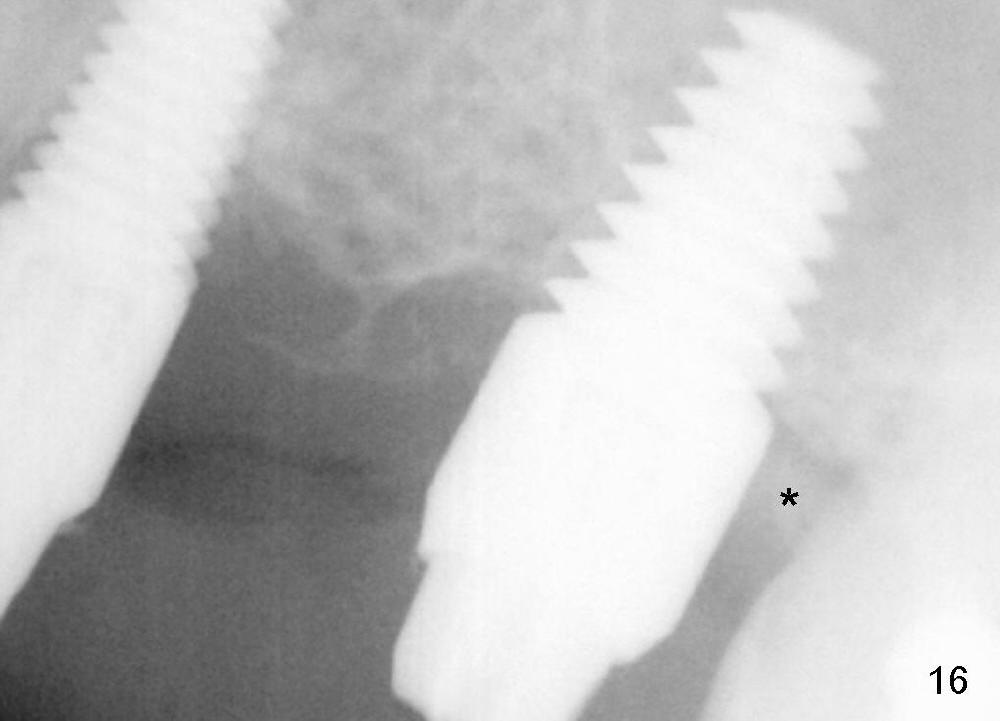

Two PAs are taken 5 months postop (Fig.15,16). Patterns of bone graft (*) between these PAs are different, which suggests presence of the graft buccal to the implant at the site of #14. Another piece of evidence of the graft is that the buccal socket heals (Fig.17 B) without implant thread exposure (Fig.19). These two implants are ready for definitive restoration (Fig.18-20). Fig.21 shows the final restoration 5 months post cementation.